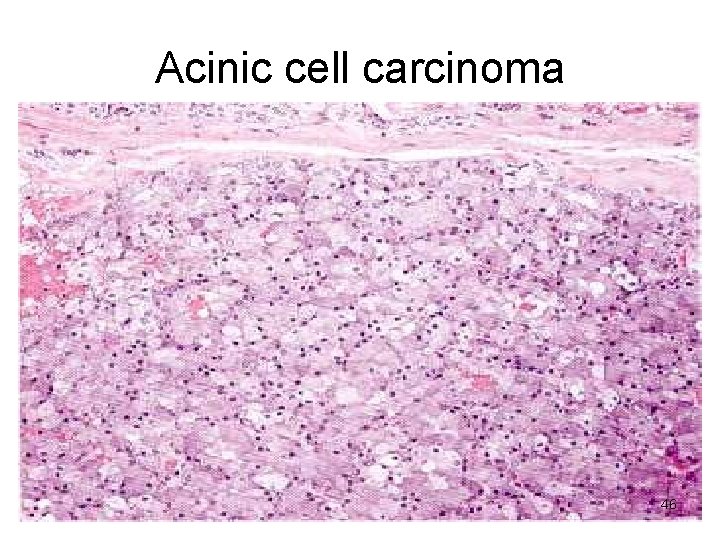

Acinic cell carcinoma Microscopy • Look like serous cells • Clear cytoplasm • Solid sheets, microcystic, glandular, follicular, papillary • Little anaplasia 45

Acinic cell carcinoma 46